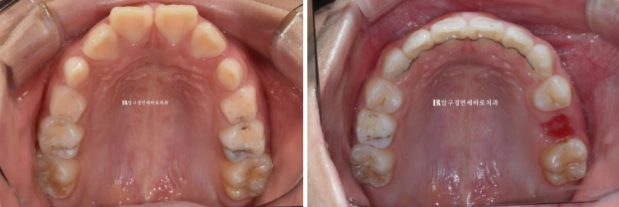

엑스레이를 보면 아직 유치가 8개나 남아있긴 합니다만 보증기간인 18개월 후면 영구치도 대부분 나올 것으로 예상이 됩니다.

악궁확장을 통해 영구치 맹출공간 확보, 윗니 돌출 해소, 앞니 배열을 목표로 장치 제작에 들어갔습니다

배열은 상당히 가지런해졌고 그 사이 유치가 여러개 빠지며 영구치가 내려오는 중입니다.

그렇게 5개월간 마지막 장치를 잘때만 끼면서 쉬는 시간을 가지다가 5개월 후 송곳니와 작은어금니가 어느정도 나와서 재제작에 들어갔습니다.

보증기간이 끝나기 직전에 17개월 차 쯔음 재제작을 한 번 더 하여 약간 돌아가있는 송곳니까지 완전히 배열을 마친 후 24년 8월에 드디어 치료를 종료했습니다.

악궁확장으로 넓어진 악궁, 그리고 가지런해진 앞니가 눈에 띕니다.

소아교정이여도 결과 유지를 위해서 유지장치가 필수입니다.

22.08~24.09

뿌리 평행도 역시 좋습니다.